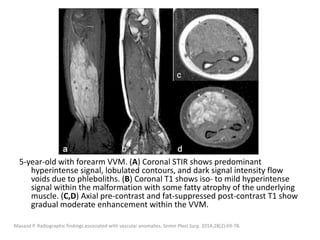

5-year-old with forearm VVM. (A) Coronal STIR shows predominant

hyperintense signal, lobulated contours, and dark signal intensity flow

voids due to phleboliths. (B) Coronal T1 shows iso- to mild hyperintense

signal within the malformation with some fatty atrophy of the underlying

muscle. (C,D) Axial pre-contrast and fat-suppressed post-contrast T1 show

gradual moderate enhancement within the VVM.

Masand P. Radiographic findings associated with vascular anomalies. Semin Plast Surg. 2014;28(2):69-78.